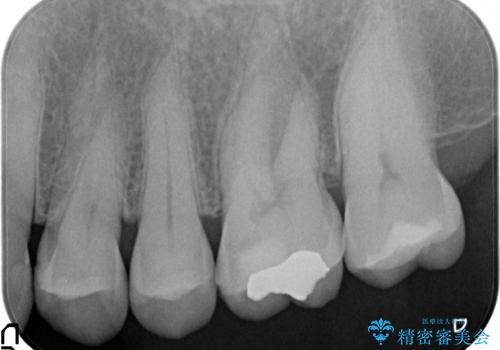

数年前に他院にて虫歯治療後しばらく痛みがあったが、やがて治まった。その後何事もなかったが、数か月前からものを咬むと痛むようになったとのこと。

検査の結果歯の神経が死んでいたため根管治療を施し、症状が治まったのを確認後オールセラミッククラウンによる補綴を行いました。

- オールセラミッククラウン…¥100,000、仮歯…¥10,000、ファイバーコア…¥20,000費用は治療当時の料金となります